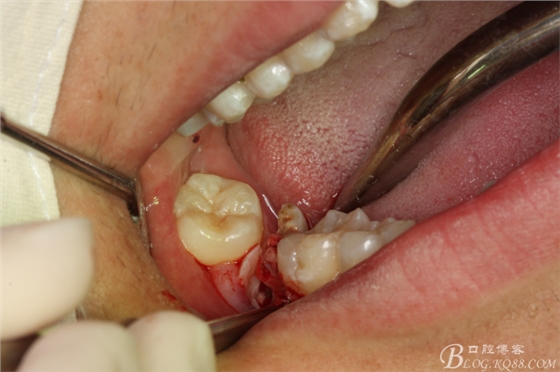

圖15.梃子放頰側(cè),以頰側(cè)骨板做支點(diǎn)。挺松47牙根。

圖16.挺出47牙根

圖17.持針器牽引出47牙根

圖18.牙根取出后,牙槽窩形狀未改變